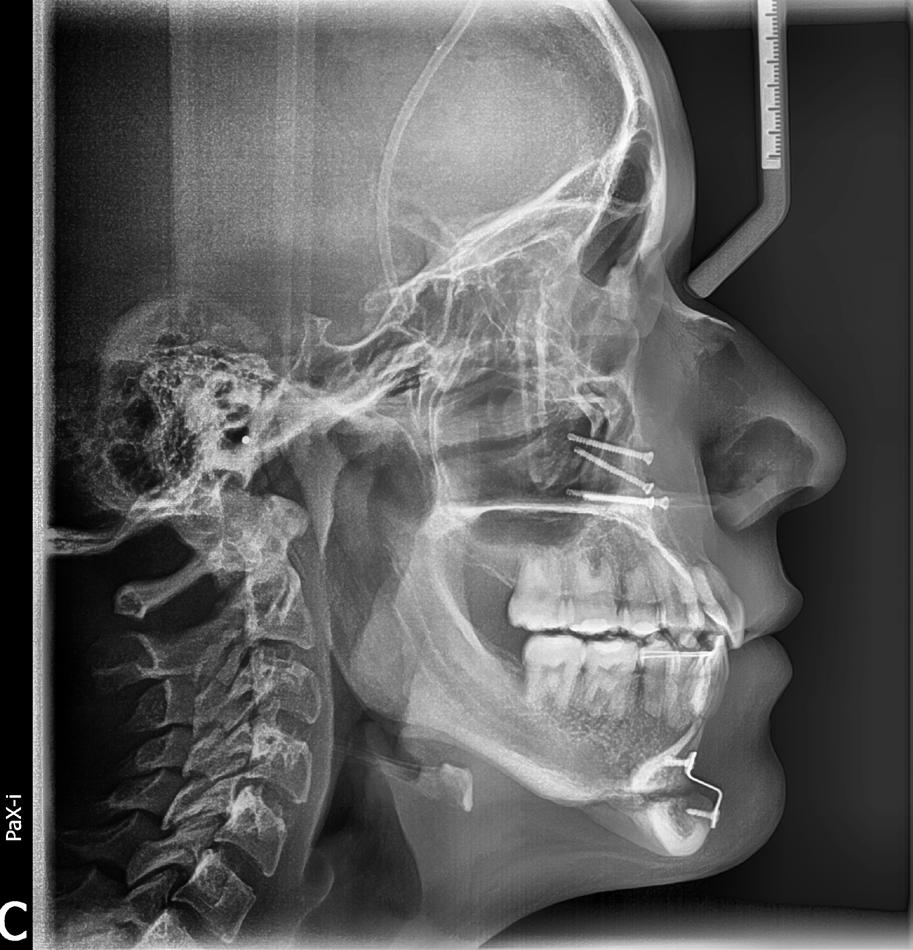

Se presenta un paciente de 18 años de edad que refiere tener hemofilia tipo A, moderado grado V. En los estudios de inicio extraorales, se observa en la Figura 1 el frente, sonrisa y perfil. En la radiografía lateral de inicio (Figura 2) se evidencian el overjet y overbite reducidos, clase I esquelética, hiperdivergencia y biprotrusión dentoalveolar.

Figura 2. Rx lateral de cráneo inicio.

Figura 8. Lateral de cráneo final, panorámica final.

El tratamiento concluyó en 2 años y 6 meses, logrando el perfil facial deseado, con clase I esquelética, clase I canina y molar bilaterales, corrección del apiñamiento maxilar y mandibular, líneas medias coincidentes, overjet y overbite adecuados, así como la realización de la genioplastia e implantes en la zona malar. En los

estudios radiográficos finales, en la lateral de cráneo, se observa la diferencia tras 2 años de iniciado el tratamiento (Figura 8), además de la radiografía panorámica final. Debido a la forma del perfil, y con el fin de alcanzar la estética deseada, se realizó la cirugía.